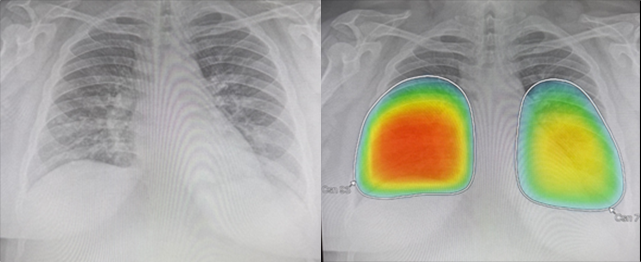

두 번째 사례는 기존 천식으로 렐바 사용 중인 30대 여성 환자로 하루 전부터 38도 이상의 고열과 심한 호흡 곤란 증상으로 내원하였다. 폐렴 의심하에 검사 시행하였으며 인공지능 판독 소견에서 양측 폐 lower lobe의 condolidation 소견이 강하게 의심되어 폐렴 진단하에 입원 치료 위해 전원한 case이다.